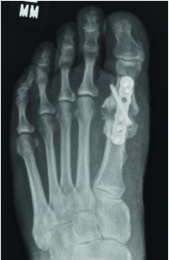

With respect to the Lapidus procedure, Barp and coworkers noted increased successful unions when using intraplate and dorsal medial plate fixation in combination with lag screw fixation in comparison to fixation with two crossed lag screws.15 These findings are consistent across the literature yet one can still achieve successful union through sound principles and two-screw fixation.

However, in the presence of osteomyelitis and deep fascial extension, authors have recommended guidelines for definitive hardware removal.33 For infection in stable osseous constructs with healed osteotomy sites and intact hardware, guidelines recommend hardware removal. One must accompany hardware removal with thorough osseous debridement of any infected bone and control of the dead space with antibiotic beads/spacers. When there is bone infection in the setting of a stable surgical site with delayed union, surgeons may choose to treat the pathogen and keep hardware intact. Unstable osseous constructs with hardware require staged reconstruction procedures with hardware removal and definitive fixation at a later interval.